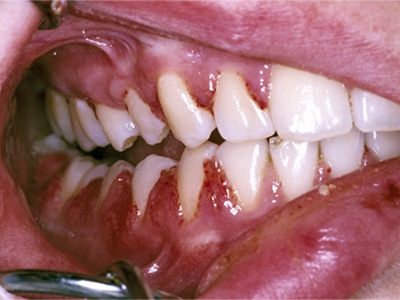

牙龈炎是发生于牙龈组织的炎症,患者可出现牙龈出血伴肿胀、发红、正常形态改变和偶尔不适等症状。本病主要由口腔卫生状况差导致,包括口腔不洁、牙菌斑等,诊断依据临床检查,治疗包括专业牙齿清洁和加强家庭口腔卫生。

牙龈炎可先引起牙齿与牙龈之间的沟(龈沟)加深,然后牙龈充血,炎症围绕一个或多个牙齿,伴牙龈乳头肿胀和易出血。一般无痛,可自行消退,也可维持轻度炎症数年。

牙龈炎常见的病因是口腔卫生差,不良的口腔卫生使牙菌斑沉积于牙齿与牙龈之间,造成龈沟加深,另外牙结石、不良修复体等也可造成牙龈炎的发生。